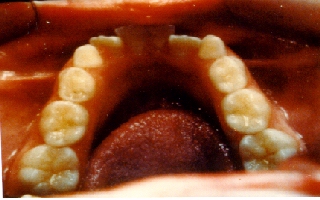

This patient had the beginnings of crooked teeth. We now know that by

utilizing modern orthodontic techniques at as early an age as possible,

many future problems can be alleviated and in some cases even totally

eliminated. For this little girl, we used a retainer called a Schwarz

appliance. The center screw in the appliance was slowly widened over

about a year's period. This changes the shape of the actual jawbone

during an active growth period. This expansion of the jawbone allows

for more room for the teeth and will either eliminate the need for

extracting permanent teeth or may even totally eliminate the need for

braces later on. |